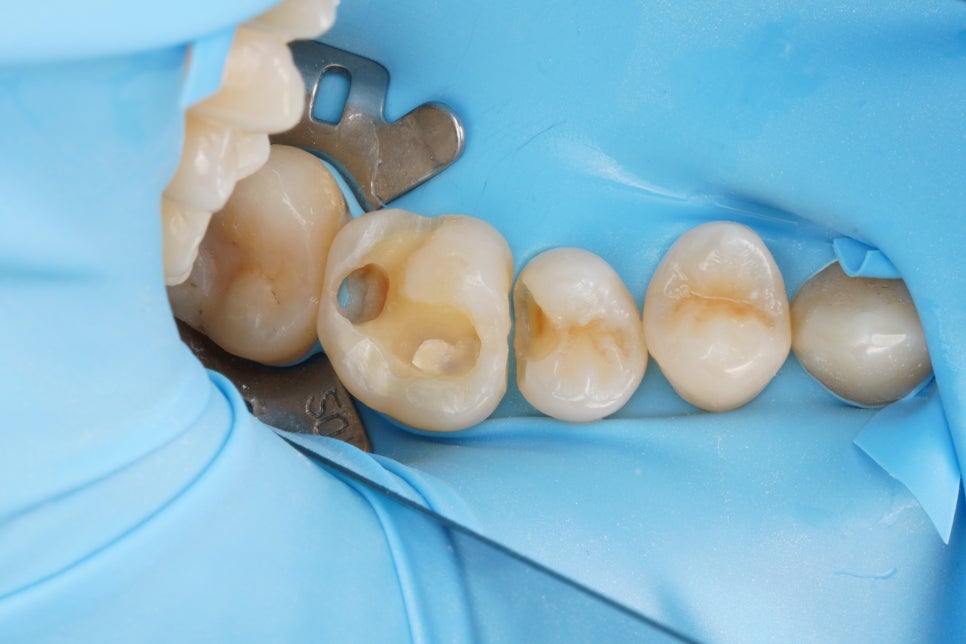

그리고 이렇게 하기 위해서는

러버댐이라는 재료를 잘 써야 해요.

러버댐을 잘 쓰는 것이

가장 중요한 첫단계입니다.

러버댐이라는 재료는

그냥 썼다고해서 다 된 게 아니라

그 목적을 이루기 위해 필요한 여러 원칙들을

하나하나 지켜야만

원하는 결과를 얻을 수 있겠죠.

어금니, 앞니 가릴 것 없이

중요한 접착의 순간에

이렇게 러버댐을 사용하는 것,

그래서 구강 내에 있는

뺨과 혀,

피와 침과 습기로부터

치아를 완전히 격리하고 방습하는 것.

그것이 교과서에 적힌 원칙이고

결과를 High-end로 유지할 수 있는

비결입니다.